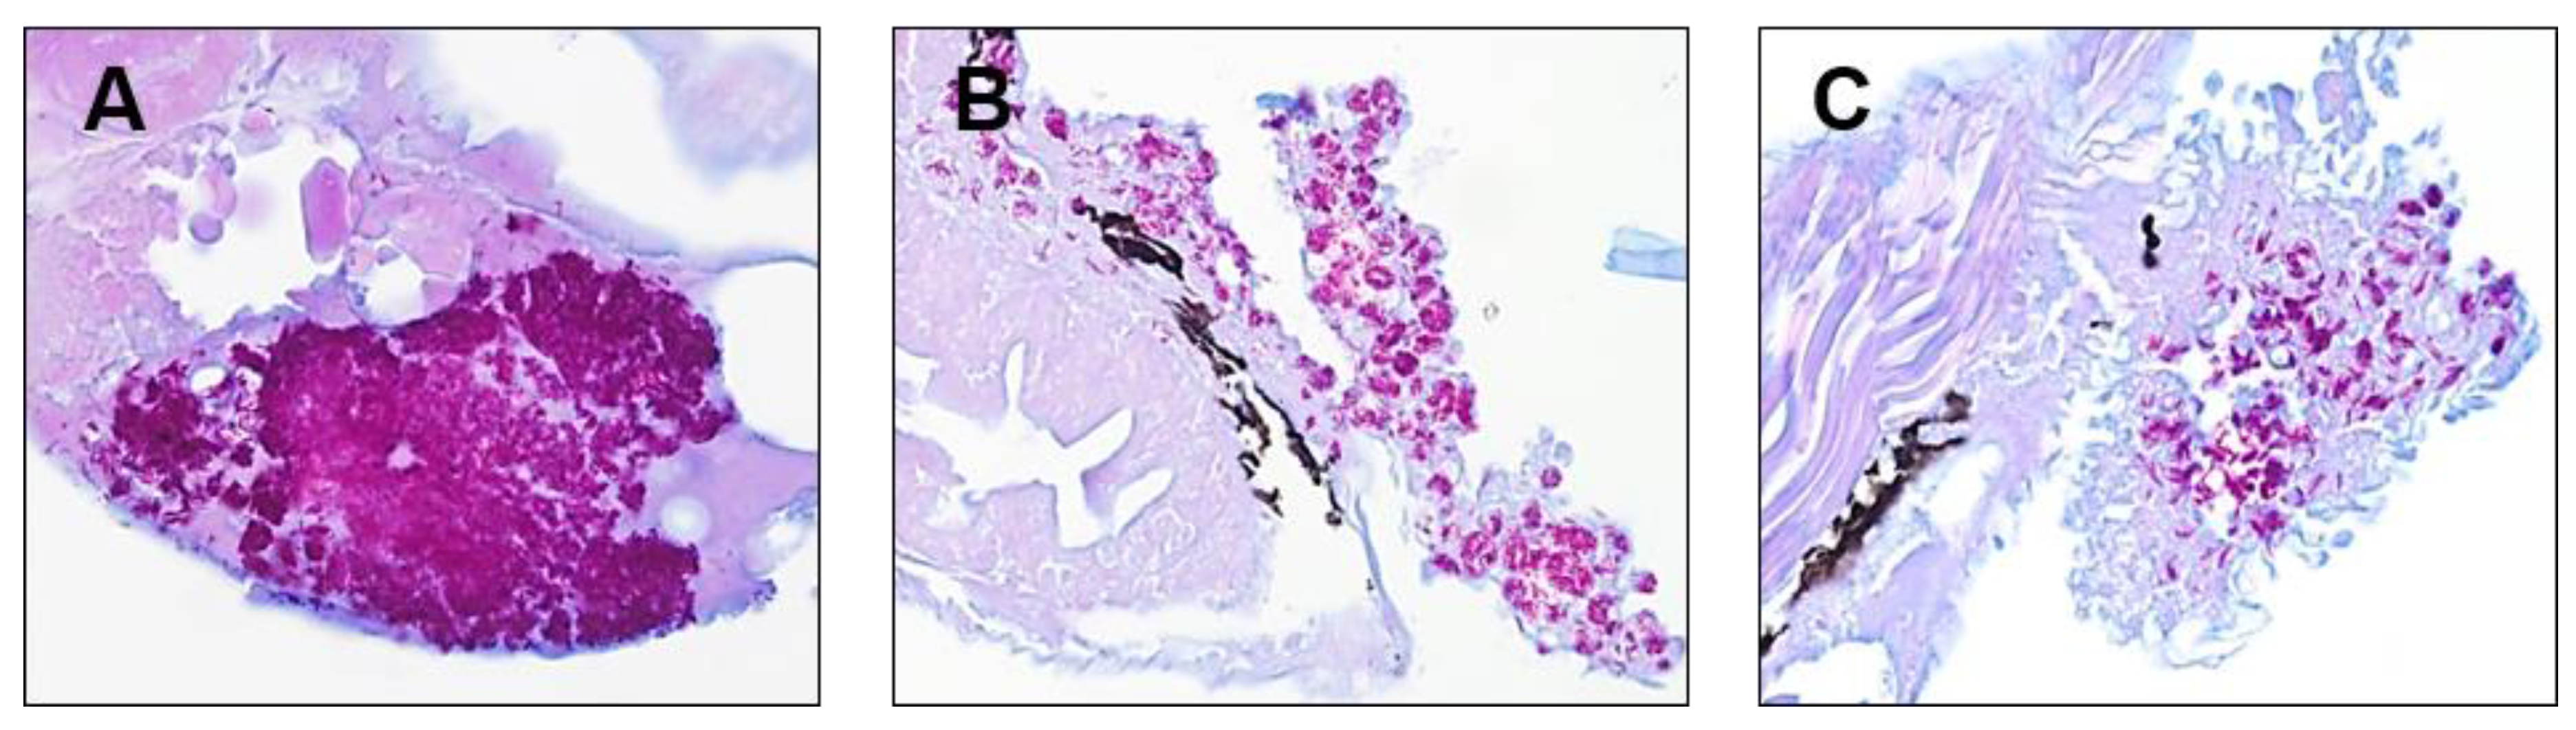

2.3. In Vivo Rifamycin O Efficacy Assessment Using ZF Embryo

4.6. Drug Efficacy Assessment in M. Abscessus-infected ZF and the Use of Ziehl-Neelsen Staining